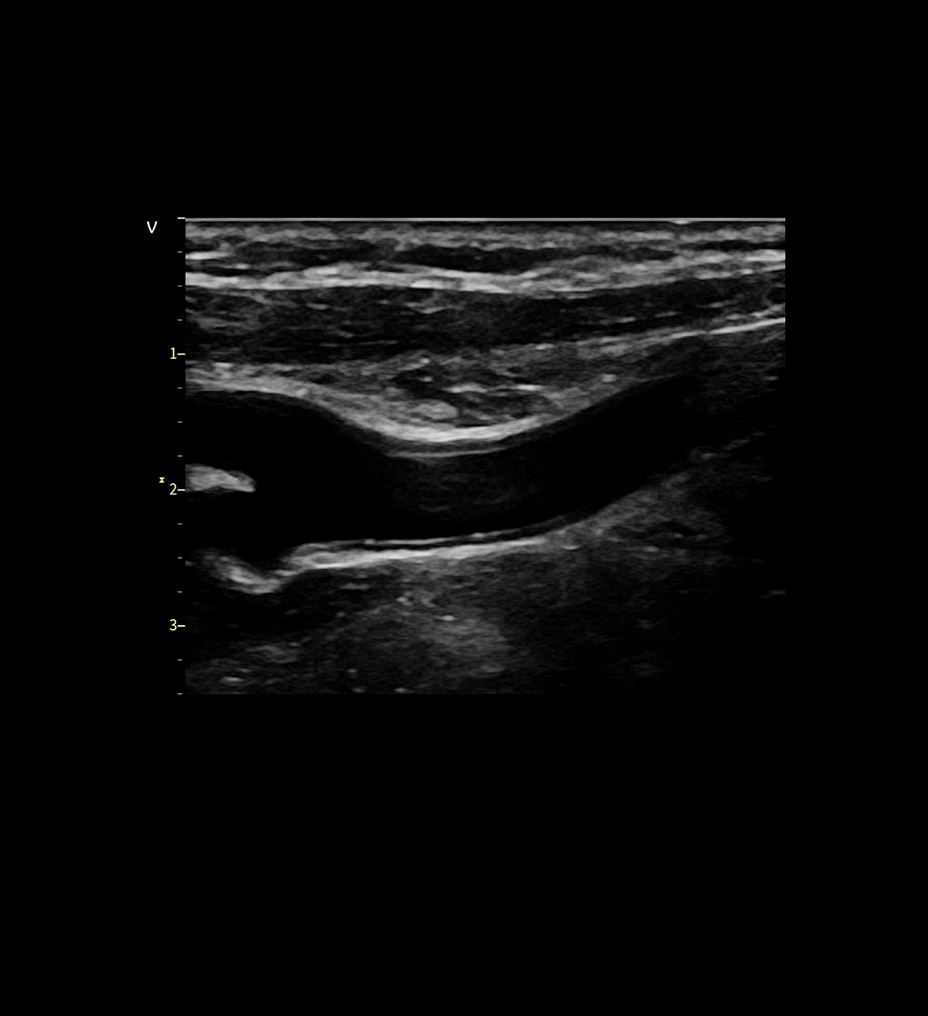

Mejore sus capacidades de diagnóstico con la innovadora cadena de adquisición de imágenes de Clarity, así como la calidad de sus imágenes en hasta un 30 %*

Cadena de adquisición de imágenes innovadora: la cadena de adquisición de imágenes de Clarity está formada por el detector del panel Atlas, el tubo de rayos X, el generador compacto de alta tensión y, de forma opcional, la reconstrucción ASiR. Ofrece una gran resolución espacial con ruido bajo y menos artefactos para satisfacer las diversas necesidades de los clientes en situaciones clínicas reales.